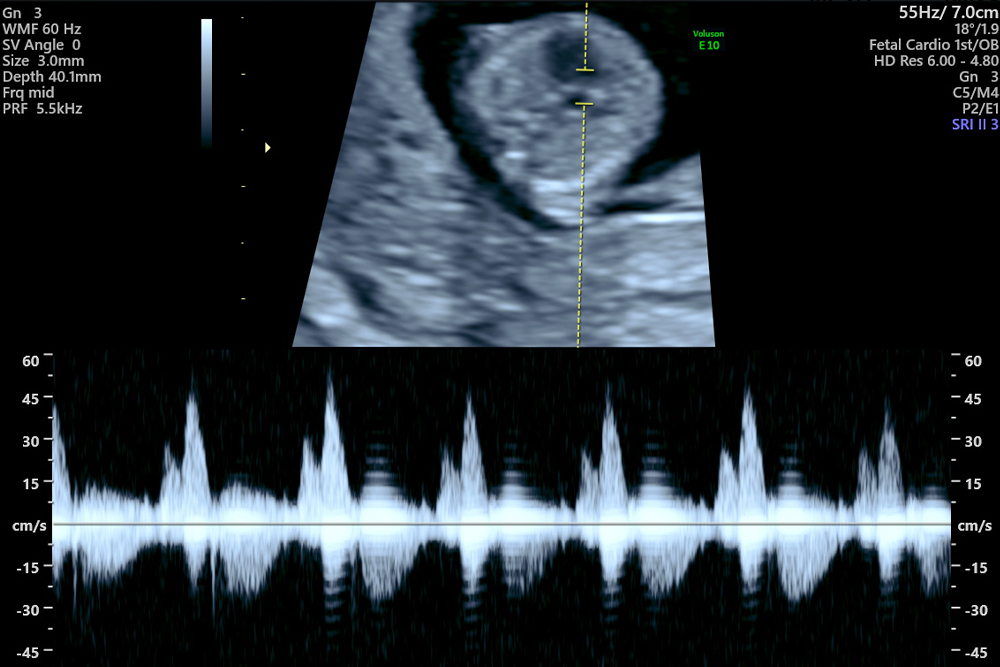

動画で見る・胎児心エコー診断 3−カラードプラーを活用した。動画で見る・胎児心エコー診断 3−カラードプラーを活用した。第3回胎児心エコーwebinar 【4ch3】完全房室中隔欠損は拡張期に。動画で見る・胎児心エコー診断。動画で見る・胎児心エコー診断 1.2.3川滝 元良DVD付 ほぼ未使用 ネーム印あり#川滝元良 #川滝_元良 #本 #自然/医療・薬学・健康